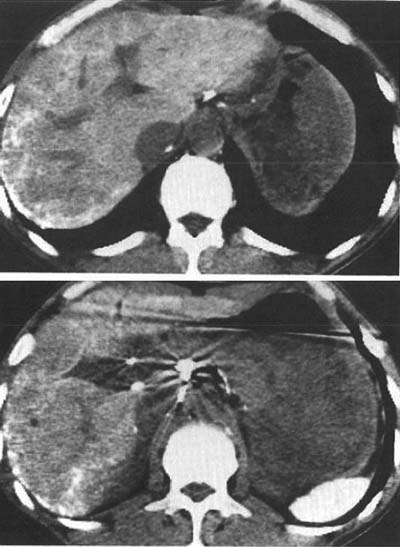

図5. トロトラスト投与39年後.沈着したトロトラストは,肝辺縁部に網目状の高吸収として認められる.肝門部のリンパ節,脾にも集積,高吸収があり,脾は高度に萎縮している.[13]

図6. 69歳男性.49年前,上肢骨折に対してトロトラストにて血管造影を施行,急性腹症にて発症.大きな低吸収の腫瘍があり(▲),その周囲にはトロトラスト沈着による網目状の高吸収が認められる.病理診断は血管肉腫. 脾の高吸収,高度萎縮(→)も認められる[9].

その優れた造影能と低刺激性から,発売直後より医師にも患者にも歓迎されたトロトラストであったが,その大きな特徴は,細網内皮系に取り込まれて肝脾,リンパ節などに長期,ほぼ恒久的に残留すること(図5),ならびに放射能を持つことである.天然に存在するトリウムは放射性同位体232Thのみで,半減期約140億年でα壊変して228Thとなる.当時,ラジウムを含む夜光塗料作業者の顎骨壊死,骨肉腫,いわゆる ラジウムガールズ事件 が既に知られており,これもα線による障害であったことから,トロトラストの安全性には当初より懸念がもたれた.既に1932年の時点で,米国医師会(AMA)はこれを指摘し,経静脈投与は認められないとしている[→関連文献].しかしその一方で,複数の論文が数年間にわたる多数症例のフォローアップの結果,安全であると報告しており[6,7],世界中で広く臨床に供されることになった.後から考えれば,この時点で放射線障害が認められなかったのは,単に腫瘍の潜伏期に比して観察期間が短か過ぎたためであった.

トロトラストの障害が初めて正式に報告されたのは,使用開始から約20年後の1947年のことである.肝梅毒腫(ゴム腫)診断目的のトロトラストによる血管造影後,12年を経て発症した肝内皮細胞肉腫の剖検例をMacMahornらが報告し,その因果関係を指摘した[→原著論文].その後も肝腫瘍,再生不良性貧血,白血病などの報告が相次ぎ,各国とも1950年代後半には次第に使用されなくなったが,1964年までに世界各国で10万人以上がトロトラストを投与された.その後の追跡結果は各国で報告されているが,例えばドイツの報告では1969~91年のフォロー期間中,トロトラストを投与された899例中410例に肝腫瘍が発生し,これに対して他の造影剤による検査を受けた対照群662例からの肝腫瘍は2例であった[8].日本の厚生省(当時)による調査でも,1966年までに124例のトロトラスト関連腫瘍が報告されている(肝肉腫が最多,潜伏期平均19.4年)[14,15].腫瘍発生までの潜伏期は16~45年とされるが,これに起因する腫瘍の発生は現在もなお続いている[9,10](図6).

トロトラストは70%が肝に集積し,誘発性腫瘍も肝に最も多い.特に胆管細胞癌,血管肉腫が特徴的であるが,肝細胞癌も発生する.トロトラストはKuppfer細胞に取り込まれて門脈域に主に集積する.ここから放出されるα線の飛程は短いが,沈着巣から範囲10μ近傍の被曝量は100Gy/年にもなり[11],門脈域周囲の細胞が特に障害されて胆管細胞癌,血管肉腫が多くなるものと考えられる.この他にも,胆嚢,肝外胆管,その他全身の悪性腫瘍の増加が知られている[12] .